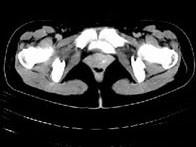

问题 女,28岁,阴道有异常液体流下,CT和MRI扫描如图,下列说诊断正确的是 ( )

选项 A、考虑为左侧输尿管异位开口 B、考虑为膀胱阴道瘘 C、MRI的T2加权像示宫颈阴道内有大片状高信号影 D、膀胱后下缘可见鸟嘴状突起 E、CT增强示造影剂由膀胱进入阴道

答案 BCDE